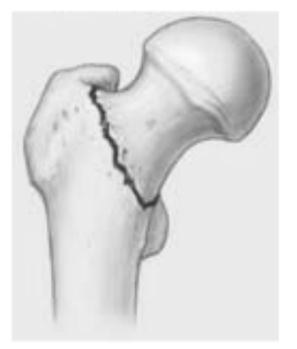

Quel type de fx de la hanche suis-je?

A

Intertrochantérienne

Vascularisation épargnée, pas de nécrose avasculaire 😎

col fémoral

Vascularisation de la tête fémorale interrompue –> NÉCROSE AVASCULAIRE

Tx prothèse hanche seulement pour ce type de fx = permet pt de marcher + rapidement